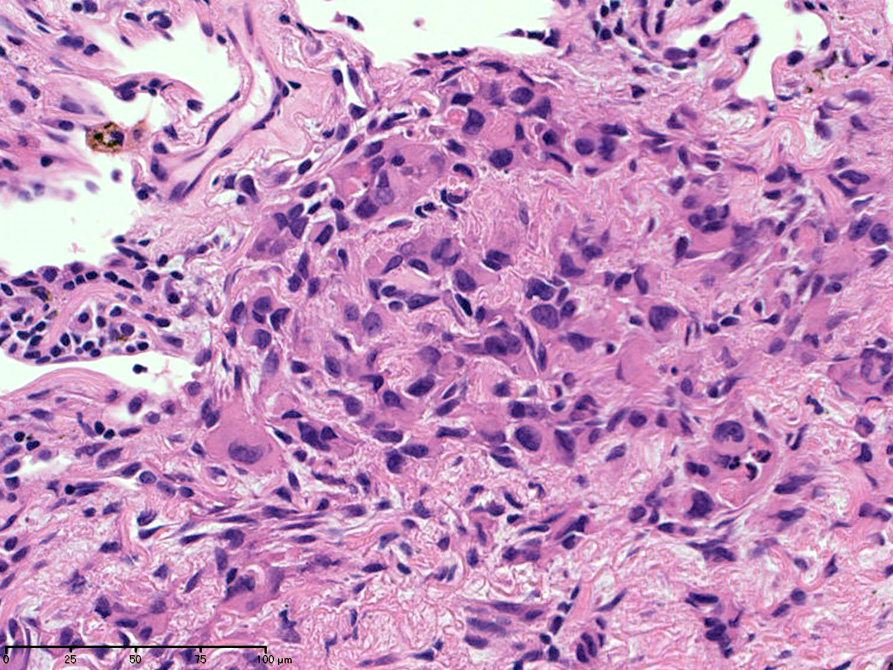

hyperchromaticな類円ないし多角の核で好酸性の広めの細胞質をもつ上皮様細胞が増殖している。右図では血管内を占拠するように腫瘍細胞が認められる。